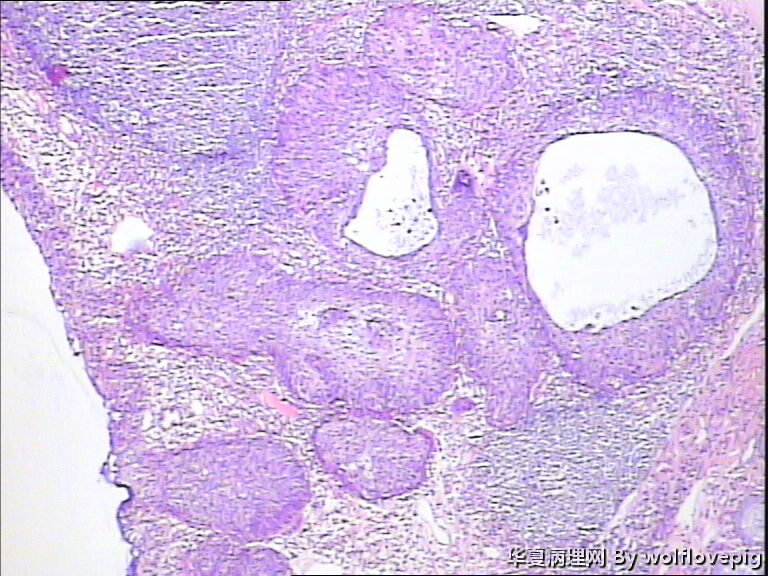

求助,宫颈!

37y

CIN3累腺

CINIII累及腺体